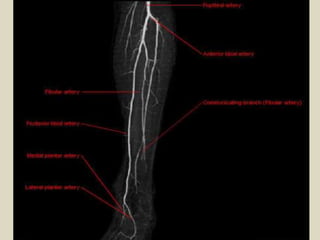

Left Lower Extremity Angiogram - labeled angiogram of arm, cross leg ... Left Lower Extremity Angiogram - 18 images - arterial anatomy of the upper extremities radiology key, imaging in lower extremity peripheral artery disease pad practice, peripheral vascular disease treatment st leonards sydney, computed tomography angiograms showing a normal lower limb, ... Left Lower Extremity Angiogram. Published by Johnny; Respiratory tract - Wikipedia The upper respiratory tract can refer to the parts of the respiratory system lying above the sternal angle (outside of the thorax), above the vocal folds, or above the cricoid cartilage. The larynx is sometimes included in both the upper and lower airways. The larynx is also called the voice box and has the associated cartilage that produces sound. The tract consists of the nasal … en.wikipedia.org › wiki › Respiratory_tractRespiratory tract - Wikipedia This infection quickly develops in the lower part of the lung and fills the lung with fluid, and excess mucus. This causes difficulty in breathing and coughing as the lower respiratory tract tries to get rid of the fluid in the lungs. You can be more prone to developing this infection if you have asthma, flu, heart disease, or cancer Torso - Wikipedia The torso or trunk is an anatomical term for the central part, or the core, of the body of many animals (including humans), from which the head, neck, limbs, tail and other appendages extend. The tetrapod torso — including that of a human — is usually divided into the thoracic segment (also known as the upper torso, where the forelimbs extend), the abdominal segment (also …

Presentation1.pptx, radiological vascular anatomy of the ...